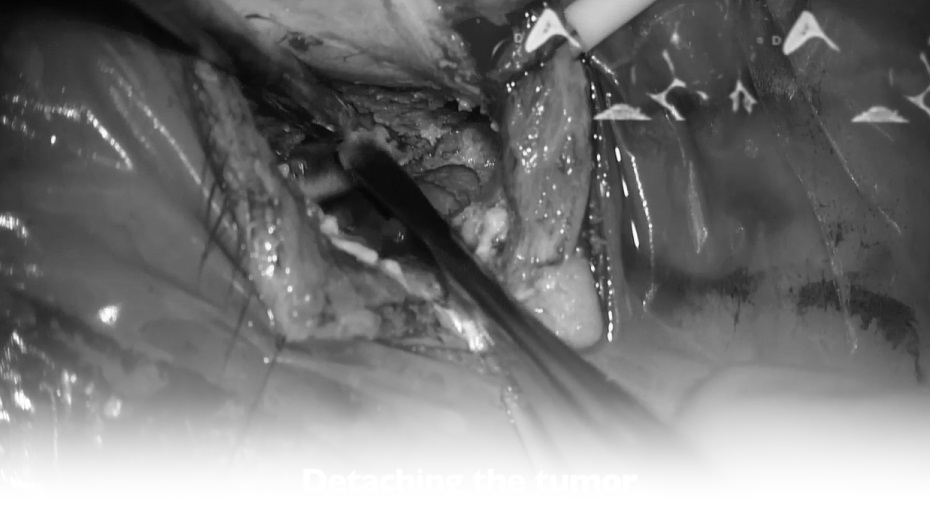

▼切除肿瘤

▼肿瘤取出